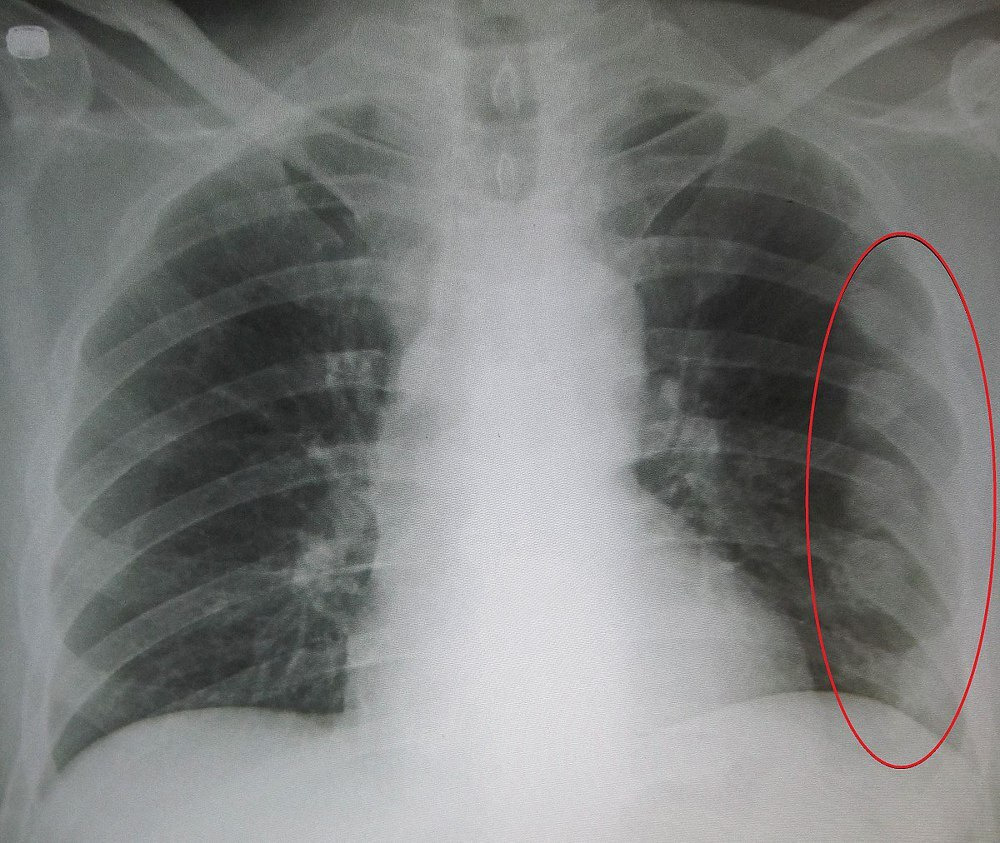

갈비뼈가 금갔을 때뿐만 아니라 모든 골절 사고는 반드시 의사의 진단을 받아야 합니다. 상황에 따라서는 X-레이 검사나 CT 스캔이 필요할 수도 있고, 경우에 따라서는 수술이 필요할 수도 있습니다. 따라서 위에서 언급한 대처방법은 임시 조치일 뿐, 전문가의 의견을 듣는 것이 가장 안전합니다.

- 복합적인 상황: 3개 이상의 갈비뼈 골절, 기흉(air in the chest cavity), 혈흉(blood in the chest cavity) 등이 있는 경우에는 복잡한 치료가 필요할 수 있습니다.